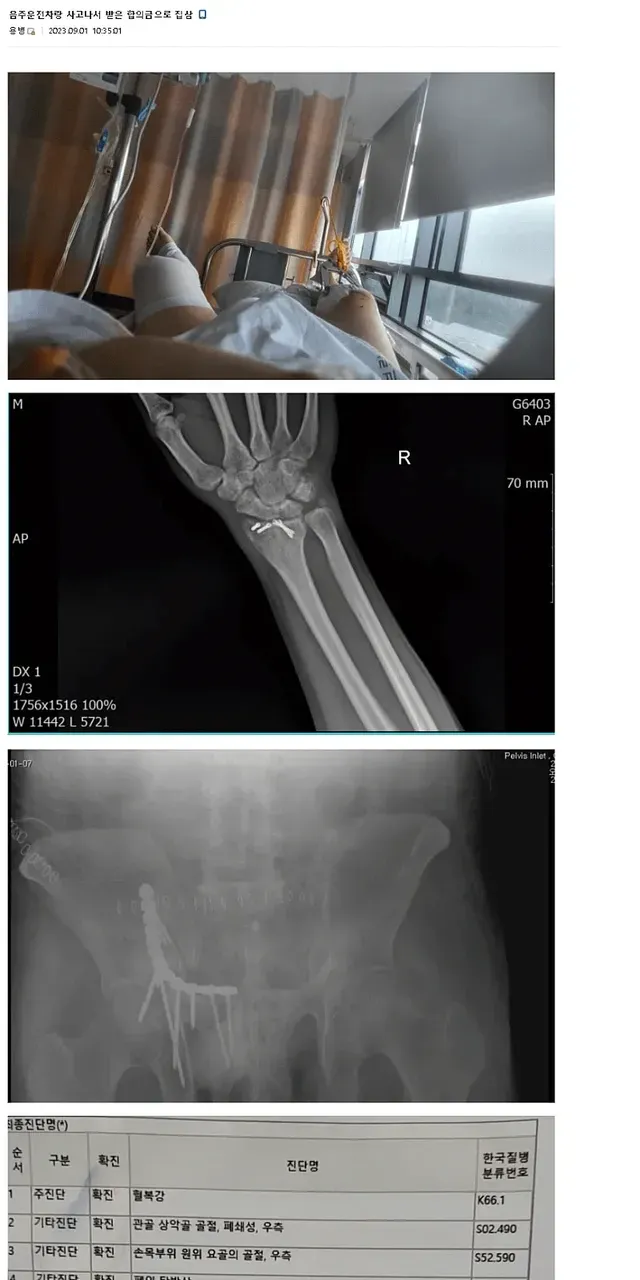

합의금으로 집, 벤츠 구매한 디씨인,,